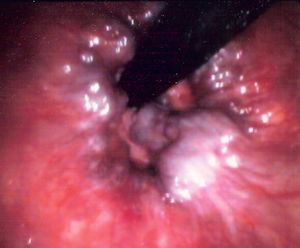

لا يظهر في المراحل الباكرة شيء خارج القناة الشرجية، ويعد المس الشرجي وتنظير الشرج الفحص الأكثر أهميةً في تقصي أعراض القناة الشرجية، إذ تظهر البواسير بوساطته بوضوح تتيح معرفة حجمها وعددها. كما يفيد التنظير في كشف أمراض أخرى مرافقة أو مسببة لبواسير.

تحدث هجمات البواسير على نحو متكرر عادةً وتختفي بالراحة والمعالجة المحافظة، وقد تصاب البواسير الهابطة أحياناً بالتخثر بسبب انحصارها وانحشارها بالمصرة الشرجية فتصير قاسية ومؤلمة جداً وغير قابلة للرد وترى خارج الشرج كتلة متورمة مؤلمة جداً حين اللمس وتتطور هذه الحالة نحو الشفاء التلقائي خلال أيام باللجوء إلى الراحة والمغاطس الدافئة وإذا لم تستجب الحالة لذلك على المريض أن يراجع الجراح لفتح الحليمة الباسورية المتخثرة وإفراغها، كما تصاب الحلم الباسورية أحياناً بالتقرح مع احتمال حدوث خمج حولها مسبباً خراجاً حول الشرج، ومن المهم هنا ضرورة التنبيه إلى أن النزف الشرجي لا يعني بالضرورة وجود البواسير بل لابد من مراجعة الطبيب للتأكد من منشئه فقد يكون ناجماً عن ورم في القناة الشرجية أو المستقيمية.